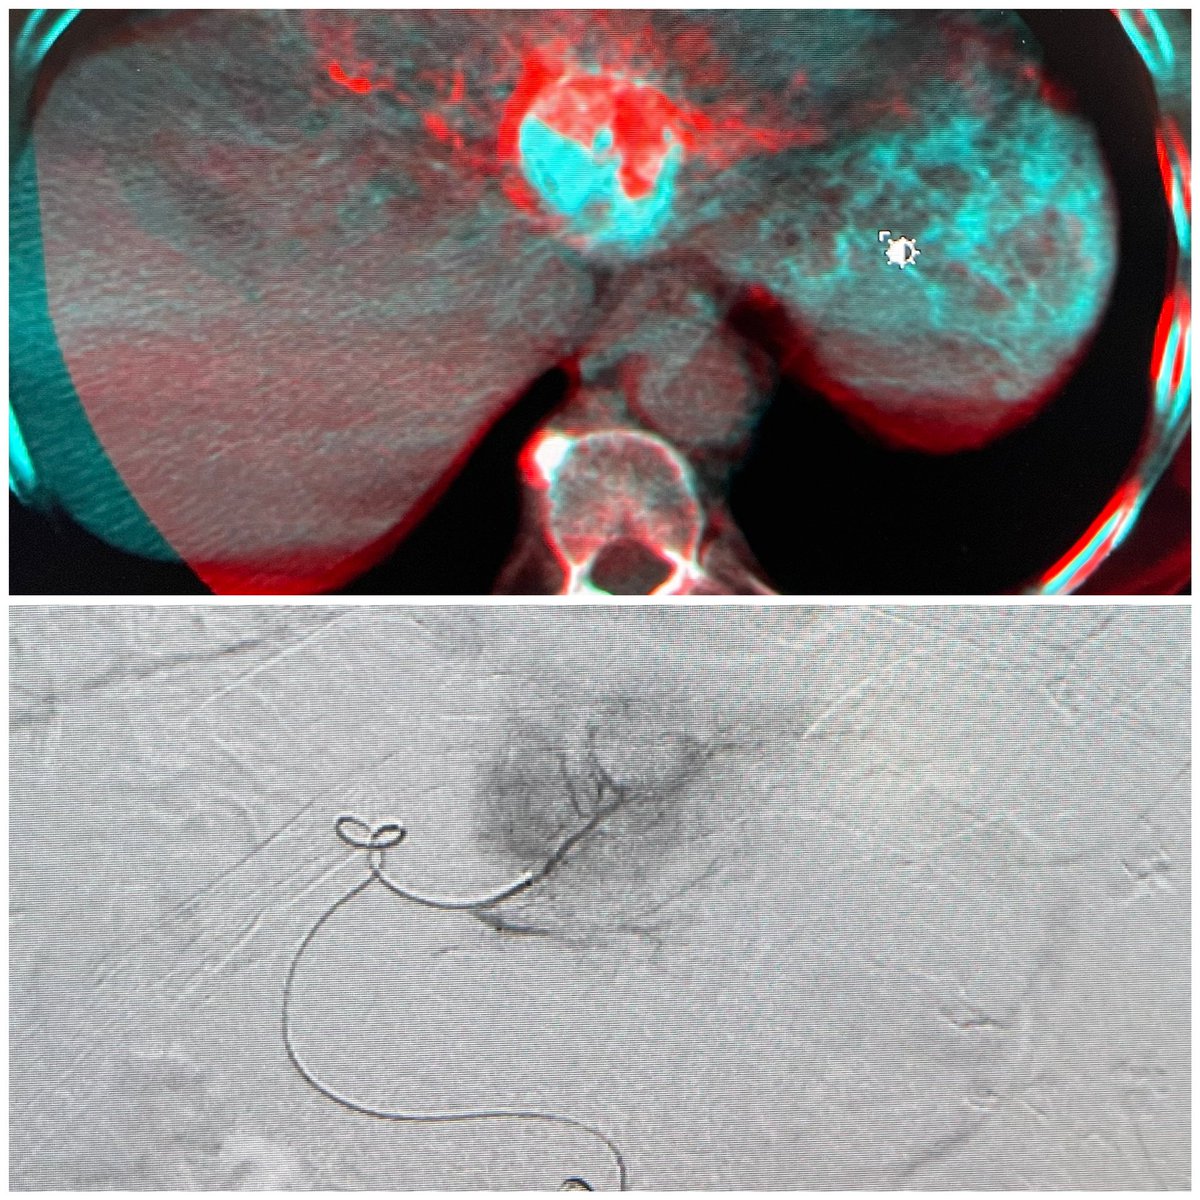

Left lateral hepatic lobe HCC supplied by two & three segmental arteries treated with high dose Y90. Fusion images show complete coverage of the tumor & SPECT CT targeted tumor dose #personalized #dosimetry #y90 #radioembolization @UTHouston_IR @UTHradiology @memorialhermann

1

3

25